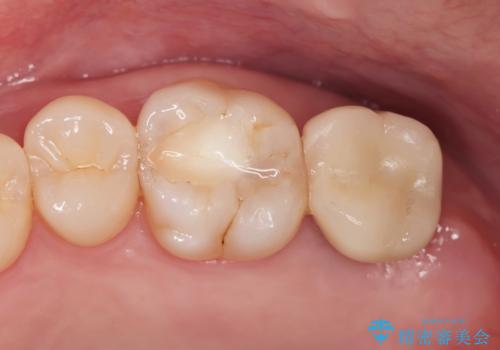

- 噛むと歯が疼いて痛い、と根管治療を希望され来院されました。

精査した結果、上顎奥歯は歯が割れてしまっており、根管治療ではなく抜歯の対象でした。